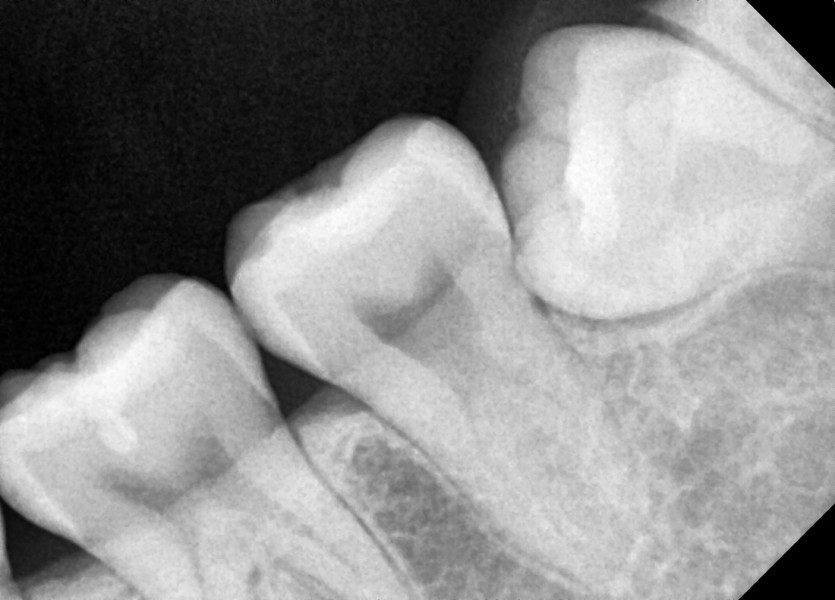

#38,48 사랑니 발치

구강 외과 전문의가 당일 발치했습니다.